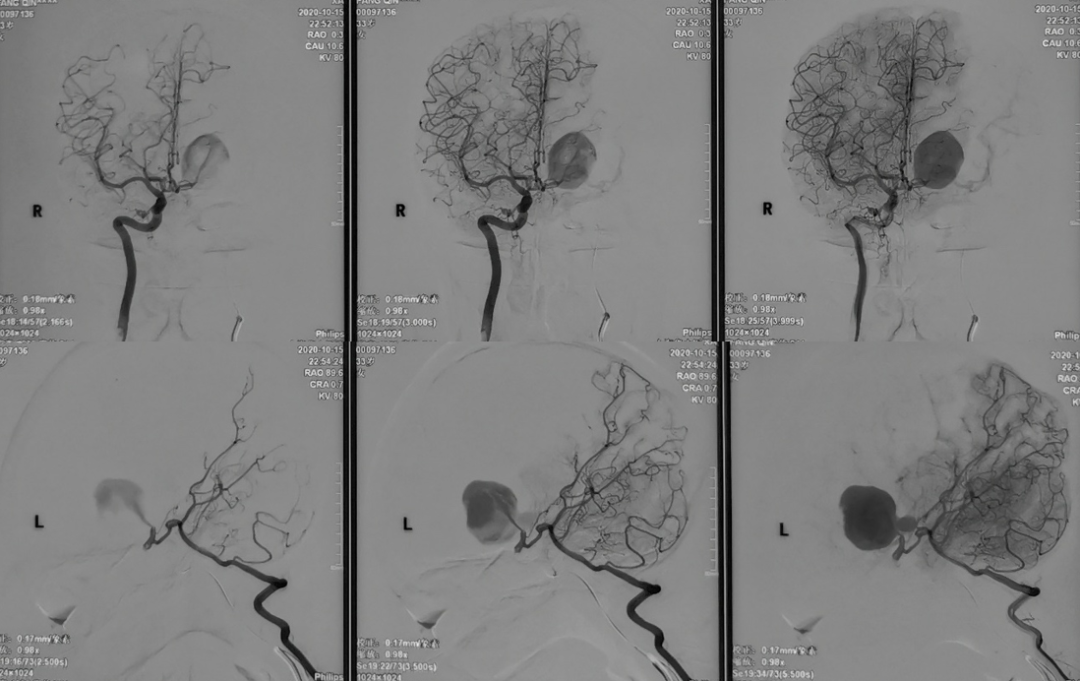

今天为大家分享的是,由复旦大学附属华山医院顾宇翔教授和倪伟医师带来的:巨大复杂颈内动脉分叉部动脉瘤一例,欢迎阅读、分享。

性别:女性,年龄:33 y.o